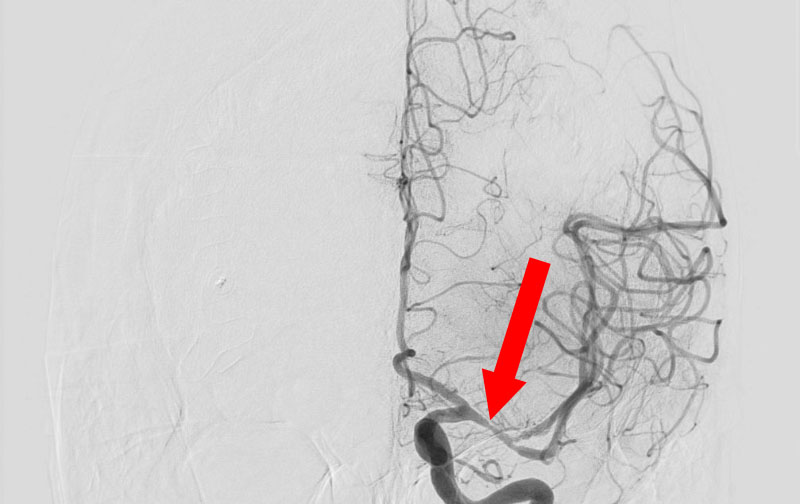

左中大脳動脈

50代

院内外来

No.1510 手術前

No.1510 手術中

No.1510 手術後